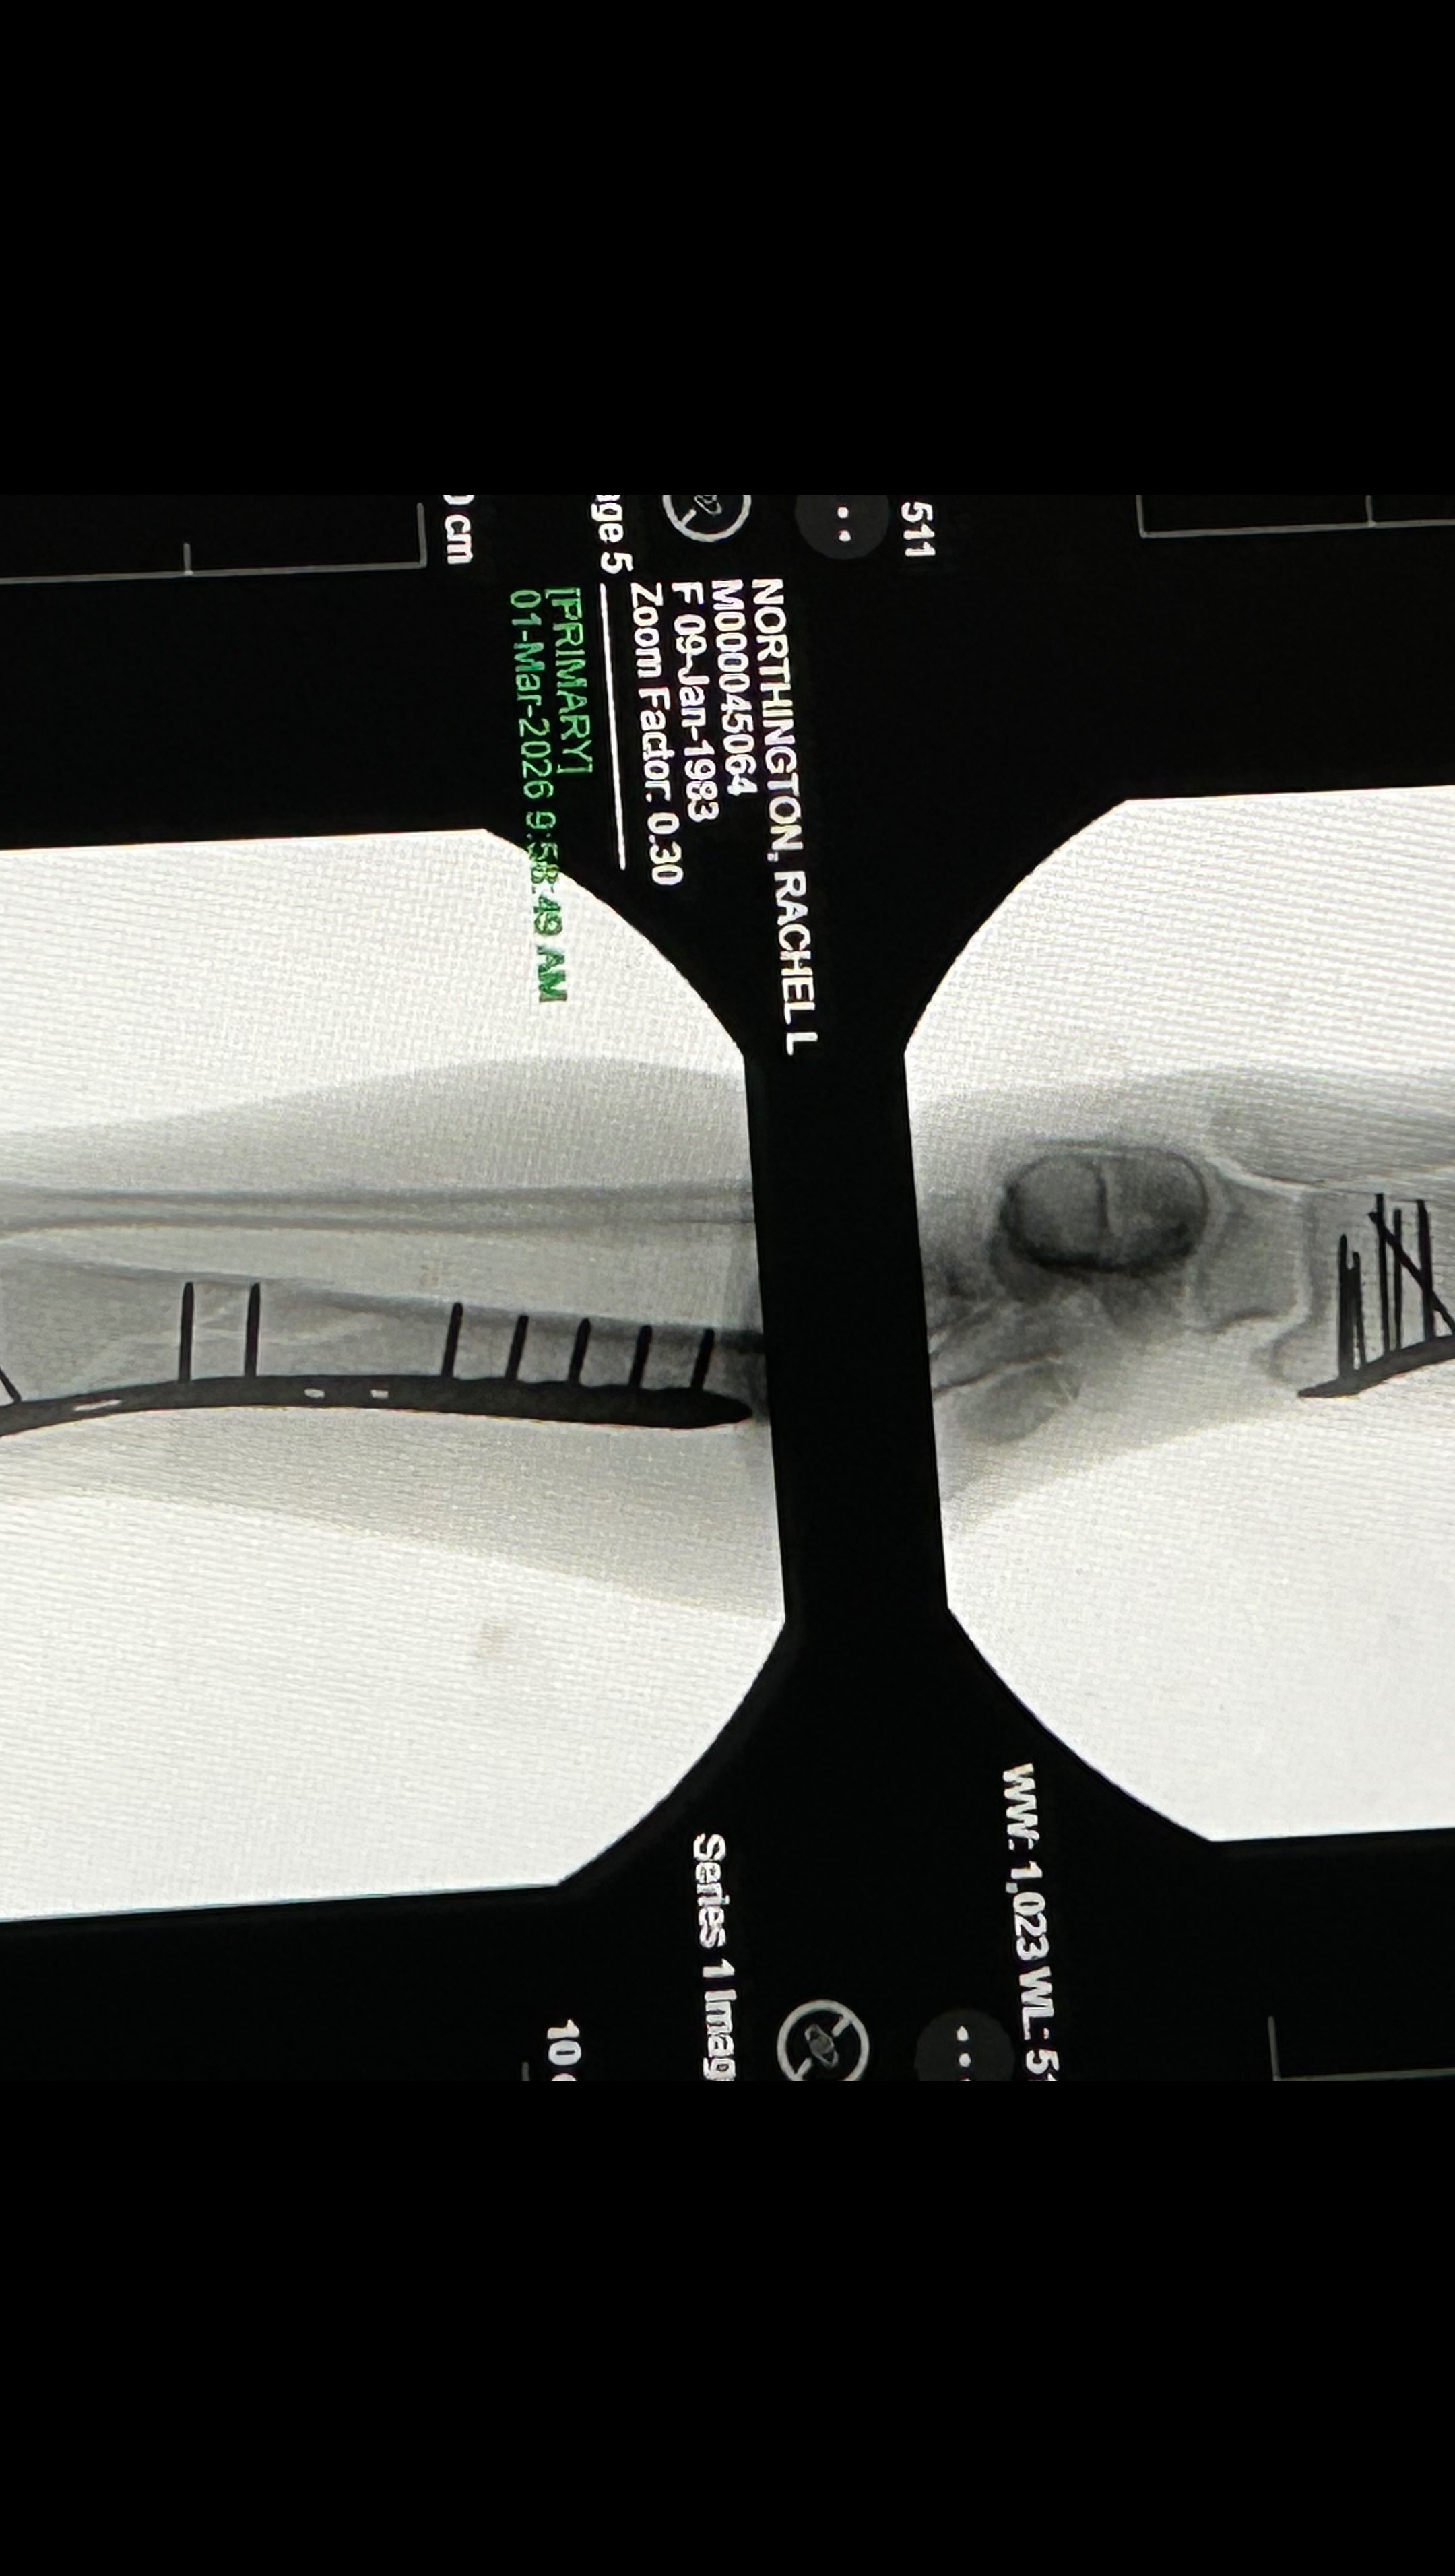

Hello my name is Rachel and I’m usually a pretty active and healthy girl. I was taken to the Murray Hospital February 15th and discharged on the 24th due to severe pancreatitis and pneumonia. I was home only a couple days and still felt very weak and tired. I attempted to go into my bathroom and somehow lost my footing and my whole body landed on my right leg and broke my right tibia and fibula (8.0 cm severely comminuted fracture of the proximal fibular shaft and 10.2 cm spiral fracture distal tibial shaft). 2 very bad fractures . It was the worst pain I’ve ever experienced! It took me 30 mins to crawl about 30 feet to my bed where my phone was to call 911 for help. The paramedics wouldn’t let me look at my leg and kept telling me to try to just lay down and relax, which was extremely hard to do. I was told my leg looked crooked and my foot was turned all the way to the side. With the help of the fire department, I was able to make it down my steps and to the ER. I had 2 doctors come in while in the ER and reset it the best they could until I could have surgery. Was supposed to be the next day but a special plate and screws had to be sent to the hospital so Sunday morning at 8am, an hour long surgery took almost 3. I now have a 9 inch place and 13 screws in my leg on one of the fractures. Depending on how the other fracture looks when I see my Ortho for follow up, I may need another surgery to put a plate on it as well. I am non weight bearing for 6-8 weeks and won’t be able to drive for no earlier than 6 months. Full recovery is a year or more. Since I am not currently working, I have applied and talked to many people about getting some sort of disability to help me keep my apartment but not getting a lot of good answers so far. I have even had my doctors send in letters stating my condition and how severe it is but it’s not getting anywhere. If anyone could find it in their heart to help me stay above water, I would greatly appreciate it!! Even a couple dollars goes a long way! All money will go to medical expenses including physical therapy, doctor appointments, medicine and the rental of medical equipment I need to get around. I didn’t want to have to make this but I’m in a rough place right now and could really use the help. Any help is appreciated. Thank you and God Bless!